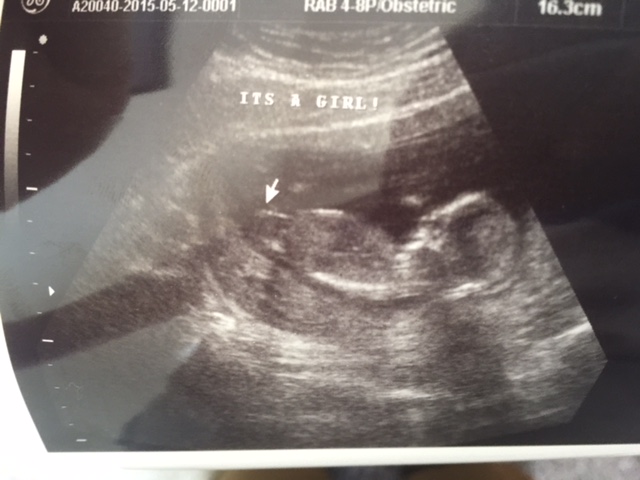

13 weeks + 1 day. Doctor said 95% chance girl. We prefer a boy. Are there any possibility to be a boy later on? Would it be too early to tell the gender?

Does look girly. Sorry you didn't hear boy x

Yes, looking girly, sorry. But congrats on baby!

I agree it looks very girly.

Looks very girly. Sorry you didn't hear boy

Very girly.

Looking extremely girly but a boy is not impossible, ultrasound is not 100% especially at this stage.